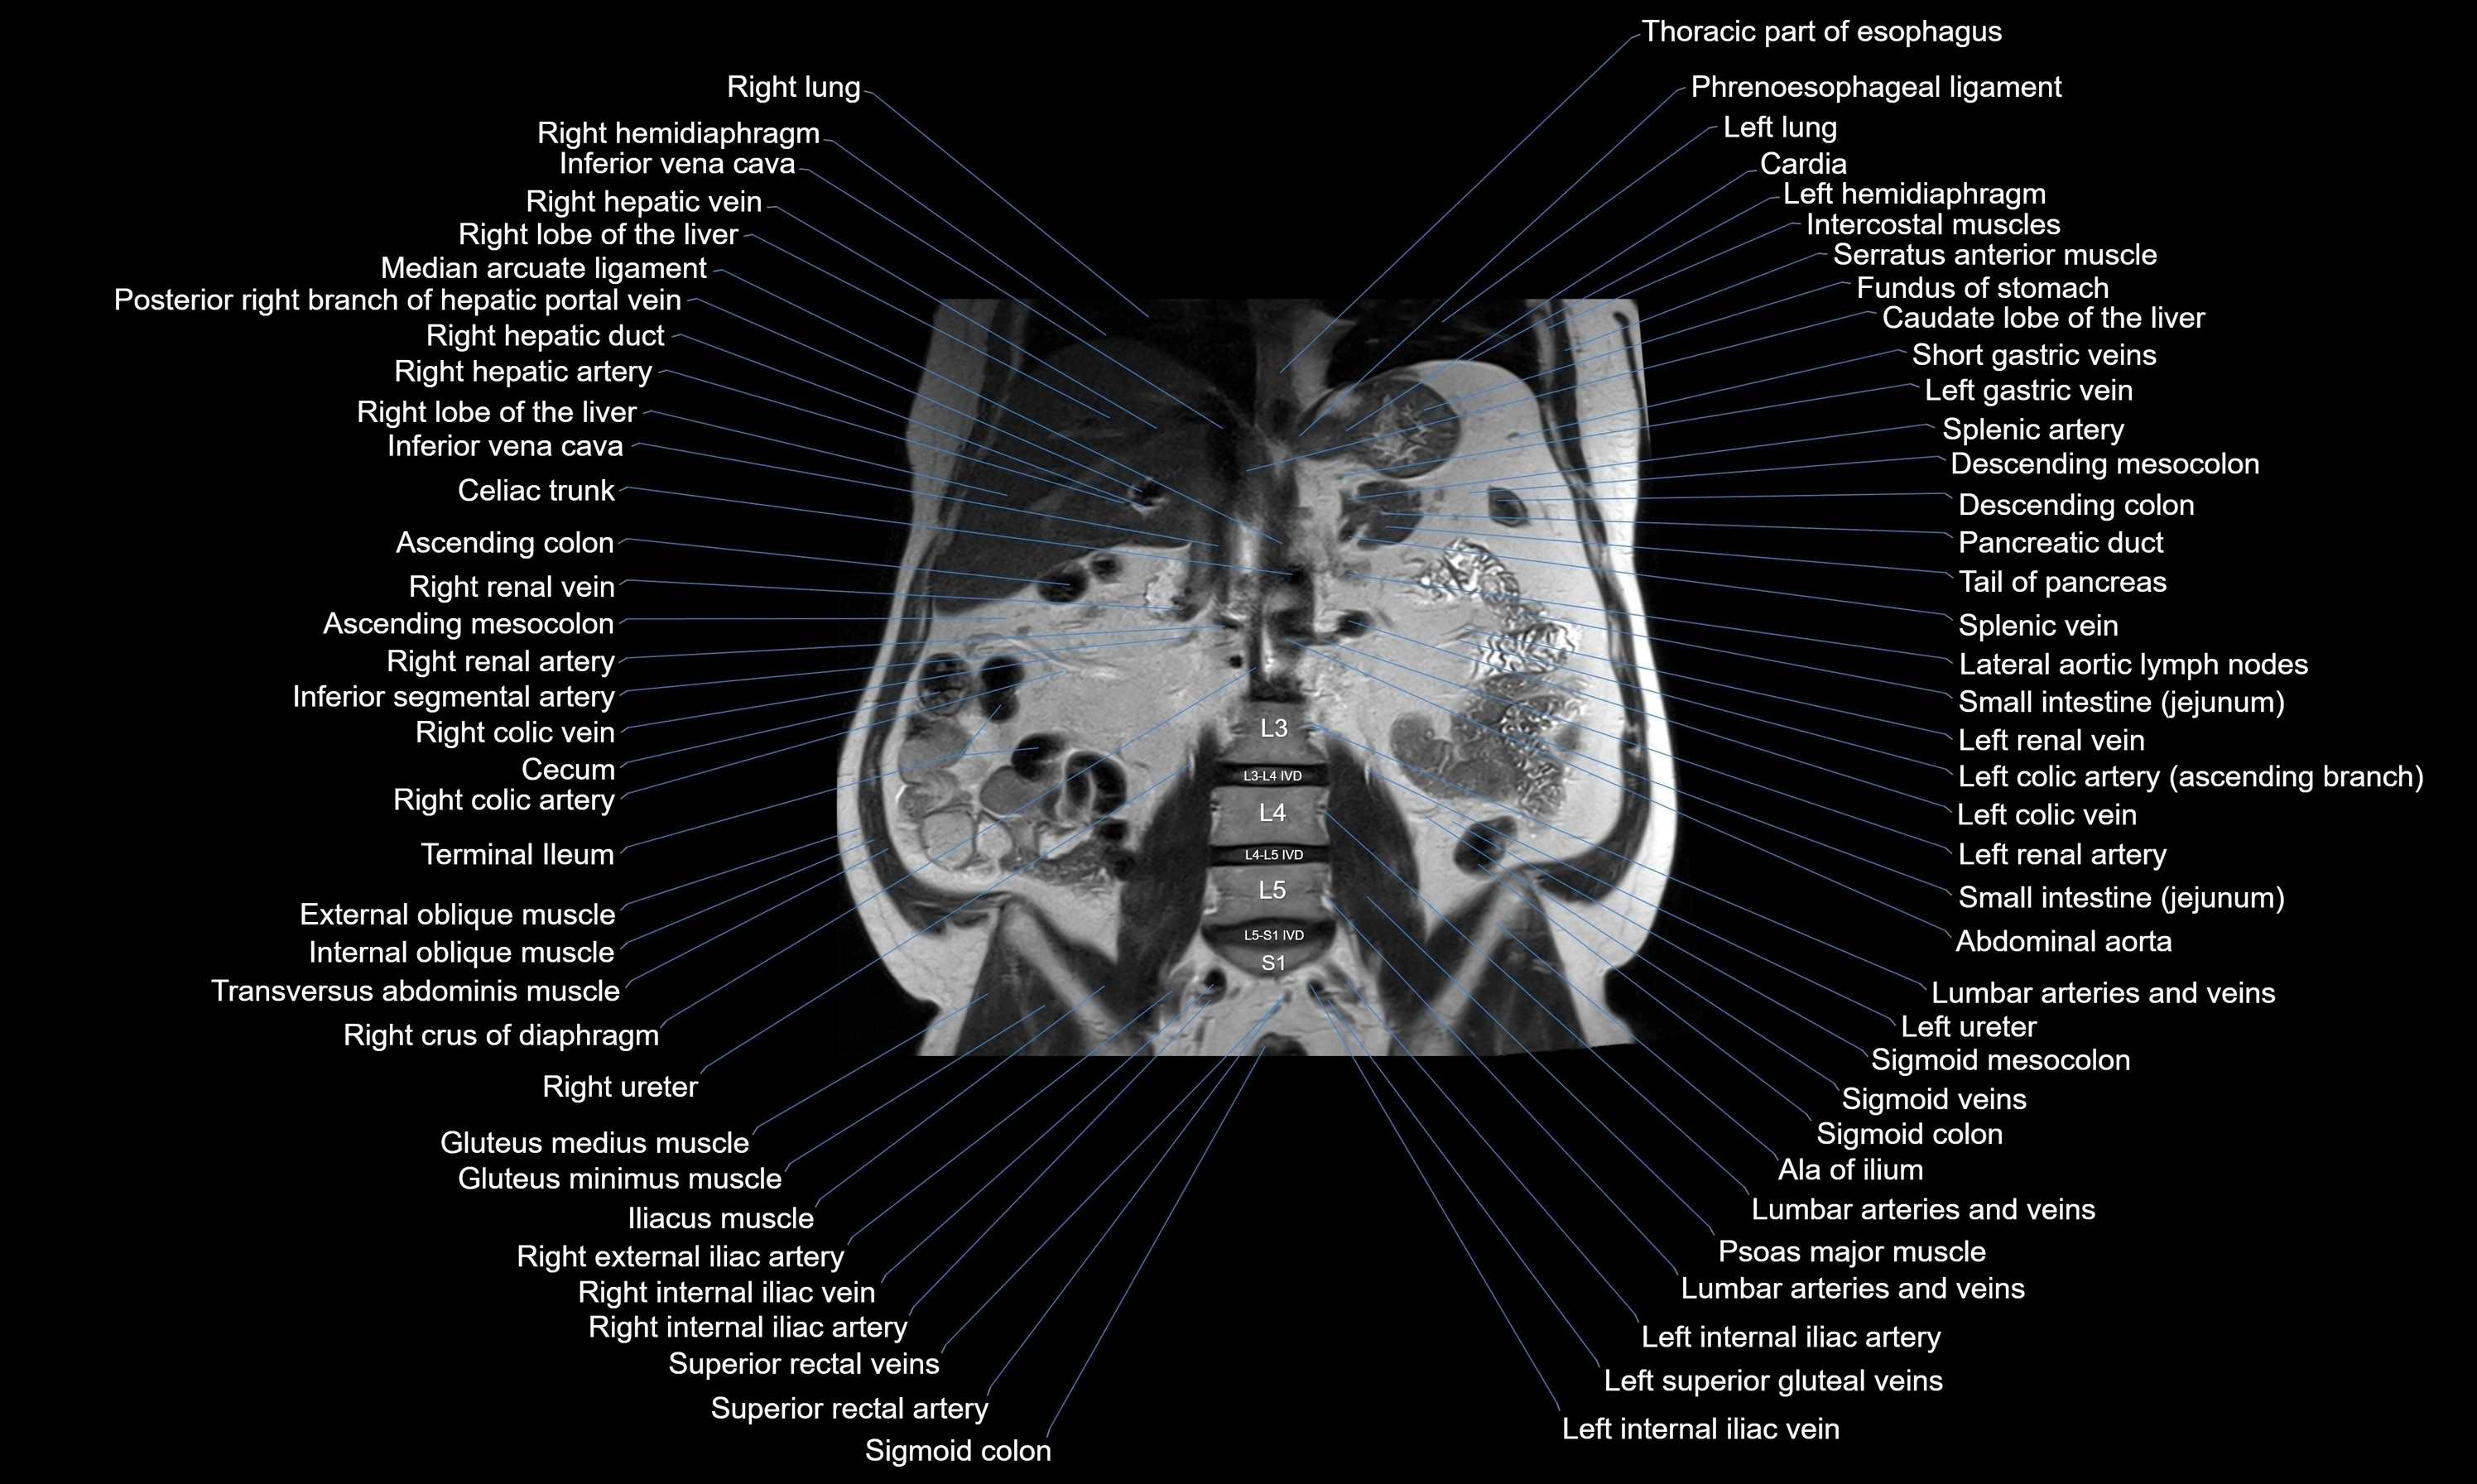

MRI images